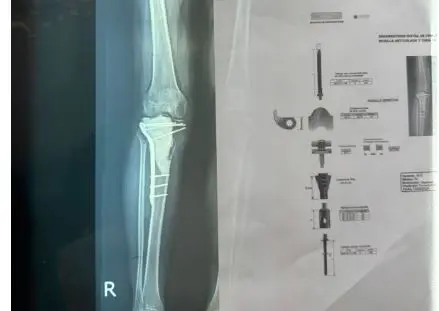

Los médicos ortopedas traumatólogos de los centros Trauma Care y Hospiten, realizaron durante el fin de semana una cirugía en el país, en la que extirparon un gran tumor de células gigantes con un comportamiento de malignidad de la tibia proximal.

Una vez realizada la intervención quirúrgica, donde extirparon el tumor de rodilla completa, colocaron al paciente una prótesis modular tumoral.

“Hicimos una recesión del fémur distal hasta la tibia, procedimiento que se extendió por siete horas”, añadió De León.

De igual forma, el especialista en trauma, dijo que para realizar el procedimiento quirúrgico fue necesario disecar los vasos, los nervios de la extremidad inferior del paciente, para poder mantener con viabilidad el miembro inferior derecho del paciente.

“Se colocó una prótesis modular tumoral que alberga una fijación a nivel del fémur, una bisagra que va a ser a su vez de rodilla y una implementación de varios módulos para conformar lo que es la tibia y una fijación intramedular, luego se hizo una reconstrucción, el paciente se encuentra en buenas condiciones de salud y este es un procedimiento que permite que el paciente conserve su miembro que tenga la funcionalidad de la prótesis y le permita realizar sus actividades tanto física como laborales y deportivas, que es la finalidad de los médicos, devolverle sus funcionalidades al paciente”, puntualizó.